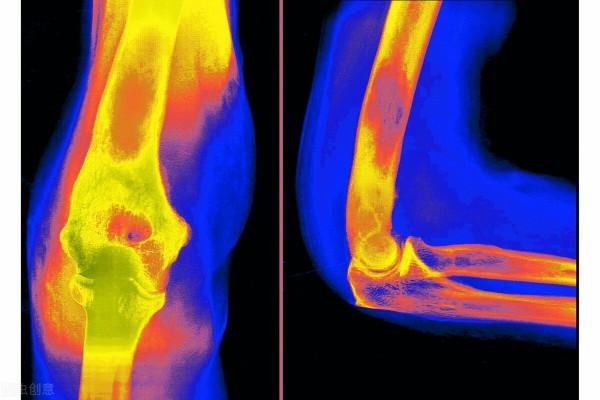

首先,我們看看,老年人群腰背部痠痛最常見的疾病有哪些?發病率最高,目前最常見的要數腰椎間盤突出了,尤其是經常過度彎腰工作的人群,該類人群經常使腰部處於負重的狀態,在加上腰椎間盤發生老化,容易使髓核突出,所以發生腰椎間盤突出以後容易腰痠、腰痛。除此之外,因為人體的神經走行在椎管之中,腰椎間盤突出以後,容易擠壓椎管之中的神經,患者會同時出現腿部的疼痛,嚴重時甚至會有手足麻木,有時患者的日常生活也會受到影響,行走時可能會出現跛行。那麼,除了腰椎間盤突出以外,那些人群還以出現腰痠、腰痛呢?工作時的不良體位、勞動姿勢、搬運重物等引起的慢性累積性損傷,遇到潮溼寒冷等物理刺激後極容易發生腰痠、腰痛。轉到腰椎間盤突出這個問題,感覺自己腰痠、背痛、手足麻木時,怎麼確定自己得了這個病呢?去相應的骨科門診或脊柱外科門診,醫生給你透過查體,開(MRI),就可以確定是不是了。

核磁共振(MRI)

綜上所述,無論是哪種疾病引起的腰痠、背痛,都需要引起我們的重視,當症狀出現時要及時去醫院檢查,不要自己主觀臆斷。得到確診後再依據臨床醫生的要求行針對性措施。對於骨科疾病,可以做MRI、CT等檢查。對於腎臟疾病,可以做尿常規,腎臟B超等檢查。對於血液疾病,可以做骨髓穿刺、血常規、蛋白免疫電泳等檢查。